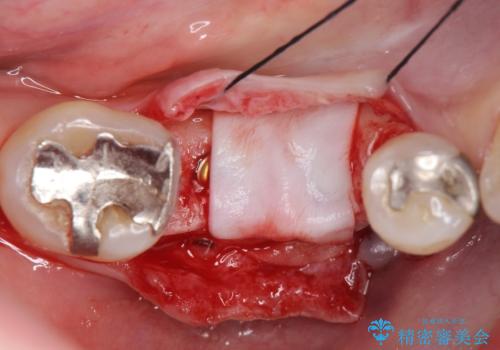

欠損部に1本だけインプラントを埋入しても大きな被せ物になってしまい清掃性が悪くなるので清掃性が良くなるように2本小臼歯用のインプラントを埋入しました。

- 抜歯、歯槽堤保存術・11万円 インプラント体、アバット、仮歯、ジルコニアクラウン・42.9万円×2 骨造成・5.5万円 e-maxインレー・7.7万円 費用は治療当時の料金となります